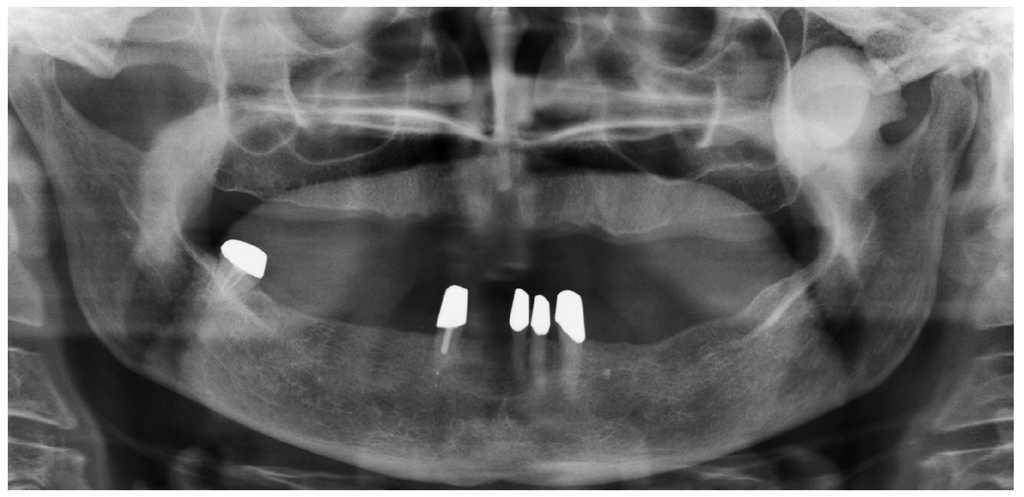

La radiografía panorámica (fig. 1) mostró una estructura de tejido óseo, densa, homogénea, con forma de hongo, bordes bien definidos y un diámetro de varios centímetros. La lesión parecía originarse en un área por encima del agujero mandibular. Un TAC de haz de cono (figs. 2 a 5) reveló la presencia de una lesión homogénea osteodensa de 3 x 3 x 2,7 cm que crecía a partir de un pedúnculo en la cara lingual de la escotadura mandibular. La circunferencia anterior alcanzaba casi a la apófisis coronoides.

Figura 1. Radiografía panorámica.